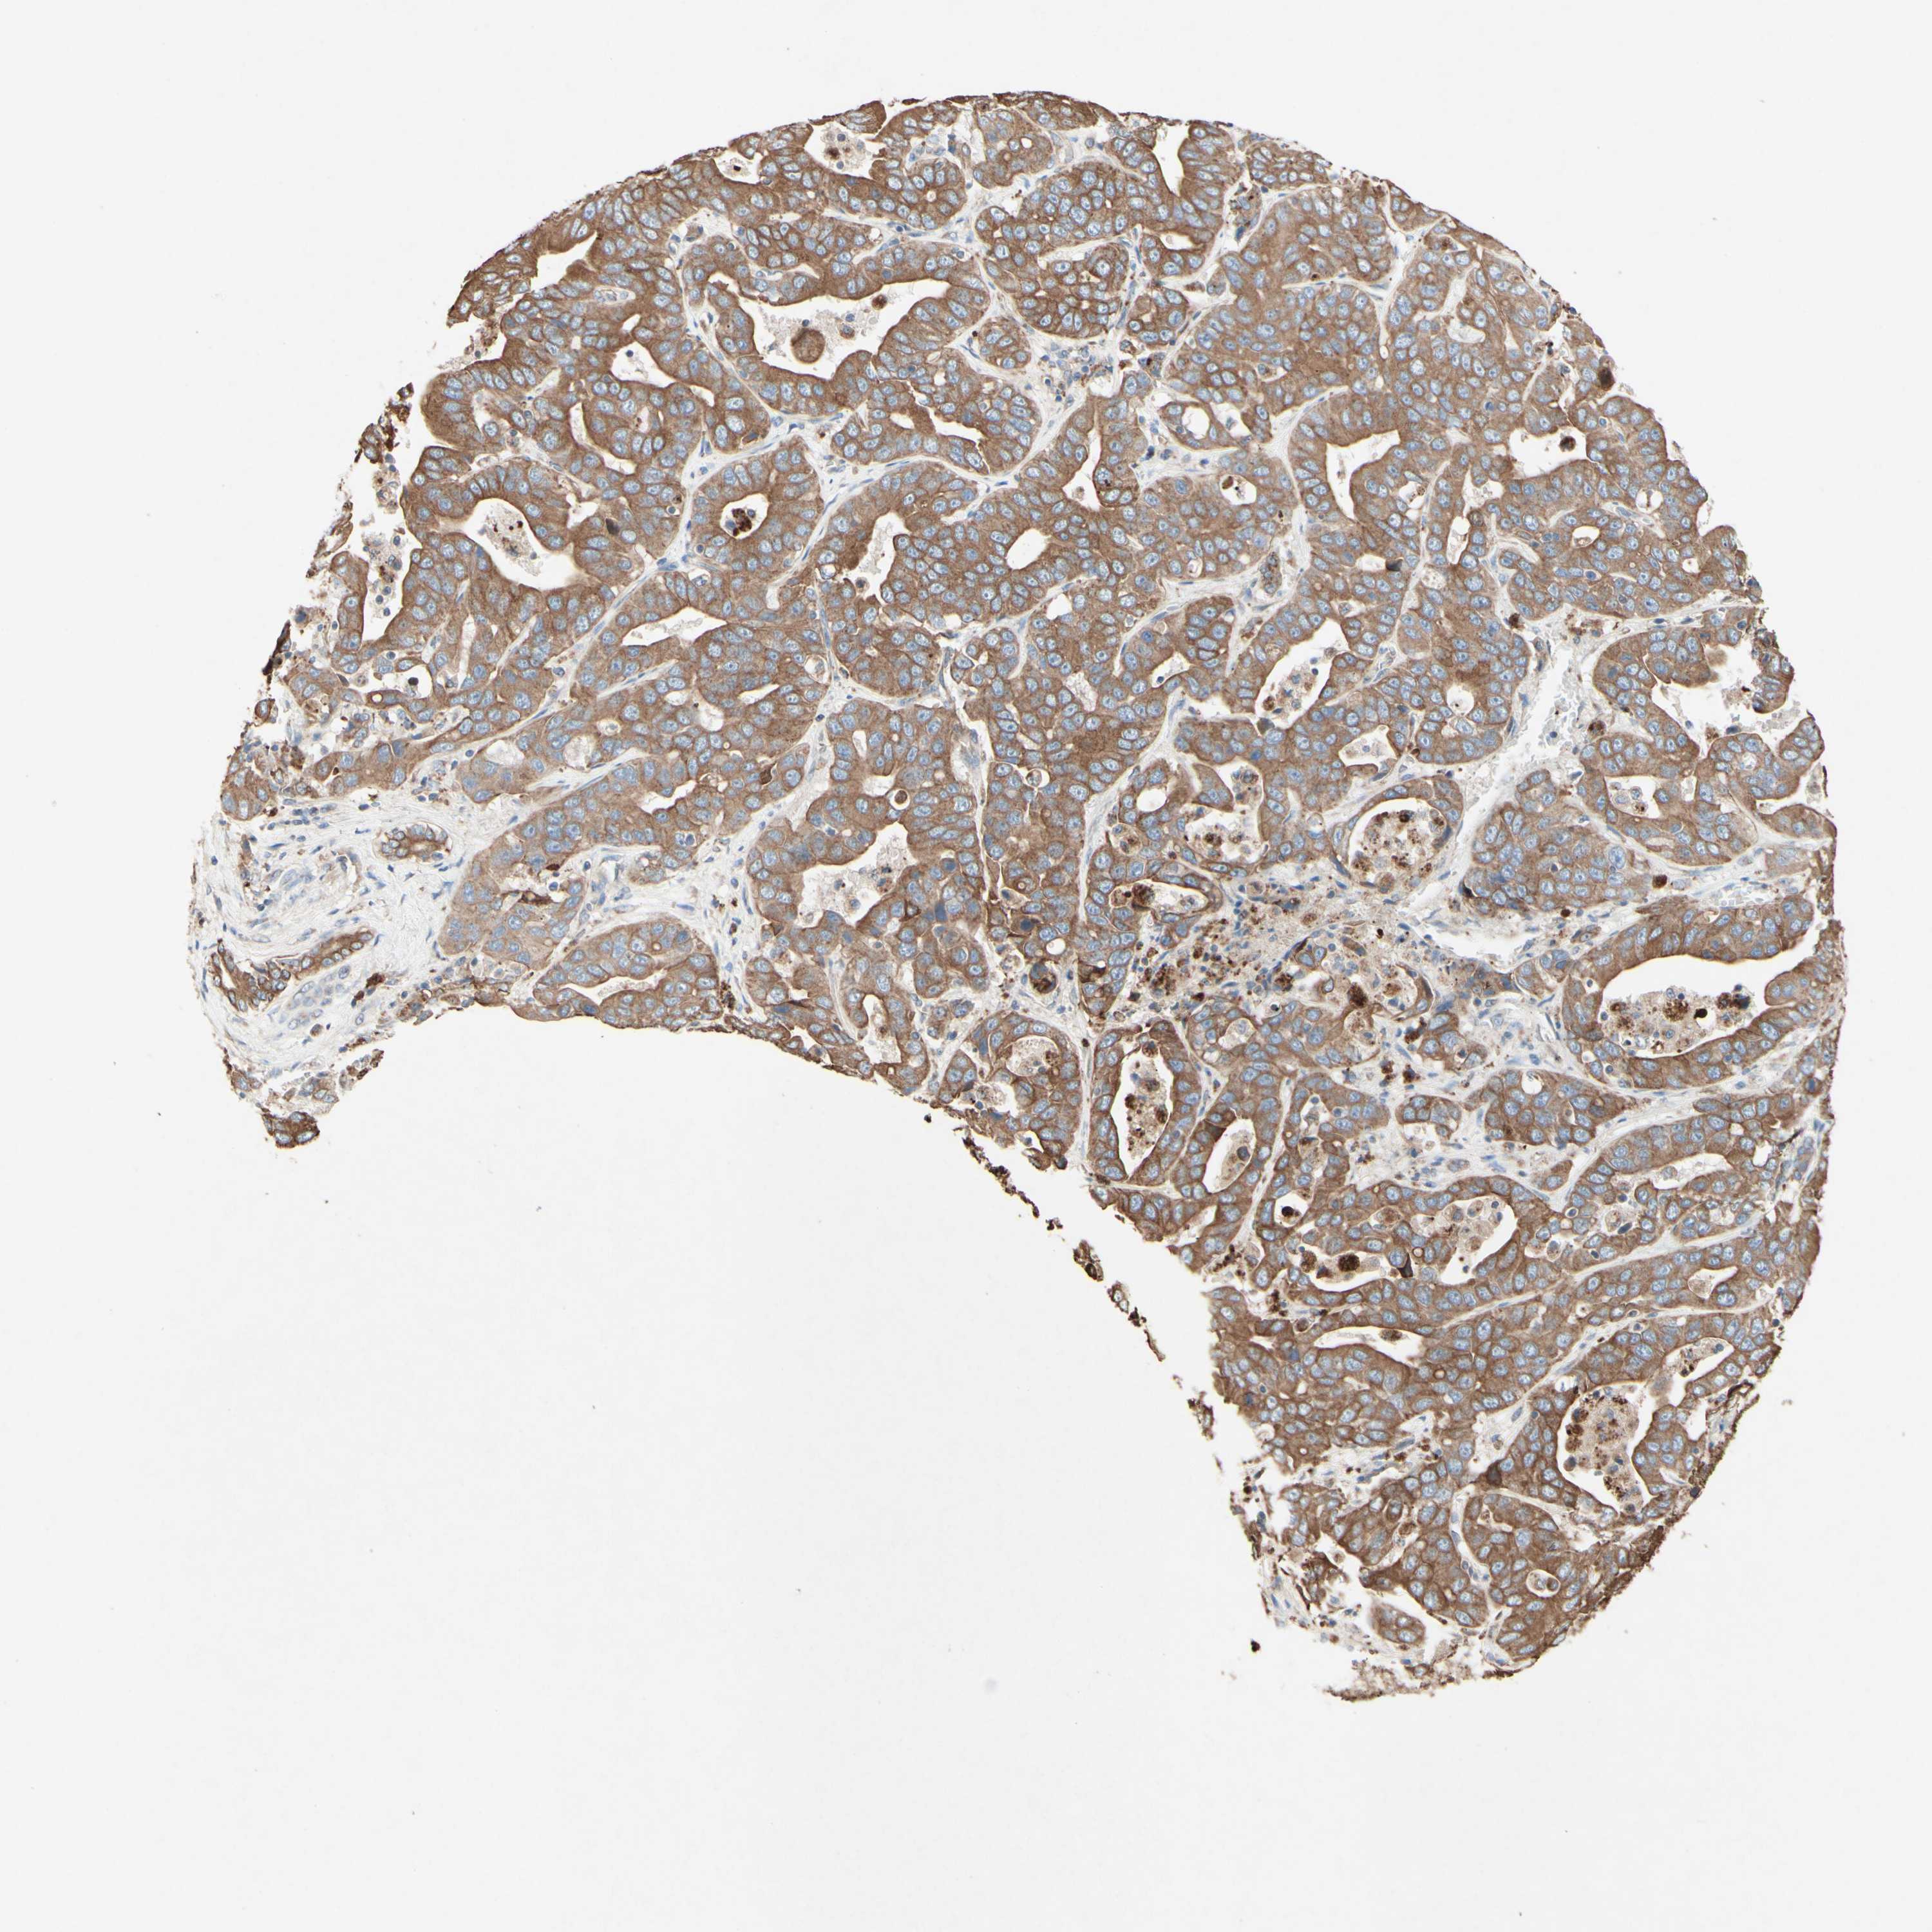

LIVER CANCER - Protein expressioni

A mouse-over function shows sample information and annotation data. Click on an image to view it in a full screen mode. Samples can be filtered based on level of antibody staining by selecting one or several of the following categories: high, medium, low and not detected. The assay and annotation is described here.

Antibody stainingi

Antibody staining in the annotated cell types in the current human tissue is reported as not detected, low, medium, or high, based on conventional immunohistochemistry profiling in selected tissues. This score is based on the combination of the staining intensity and fraction of stained cells.

Each image is clickable and will lead to virtual microscopy that enables deeper exploration of all samples and also displays staining intensity scores, fraction scores and subcellular localization as well as patient and tissue information for each sample.

Antibody HPA010008

Antibody HPA010665

Staining

High

Medium

Low

Not detected

Intensity

Strong

Moderate

Weak

Negative

Quantity

>75%

75%-25%

<25%

None

Location

Nuclear

Cytoplasmic/membranous

Cytoplasmic/membranous,nuclear

Cholangiocarcinoma

Carcinoma, Hepatocellular, NOS